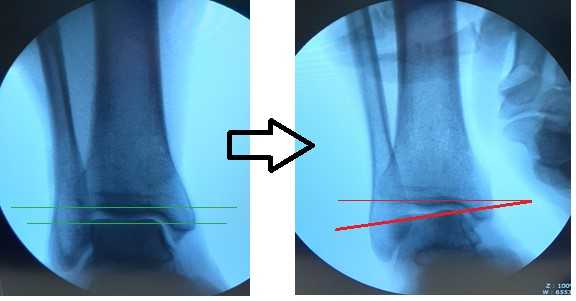

После восстановления латерального связочного комплекса по Брострому в модификации Голда и фиксации межберцового синдесмоза винтом производится оценка стабильности голеностопного сустава при помощи вальгус—стресс теста под контролем ЭОП.

Гипермобильность голеностопного сустава устранена, положение таранной кости остаётся неизменным несмотря на приложение вальгусной нагрузки.

На рентгенограммах видно что после удаления позиционного винта взаимоотношения большеберцовой и малоберцовой костей остаётся прежним, что свидетельствует в пользу того что лечение прошло успешно.